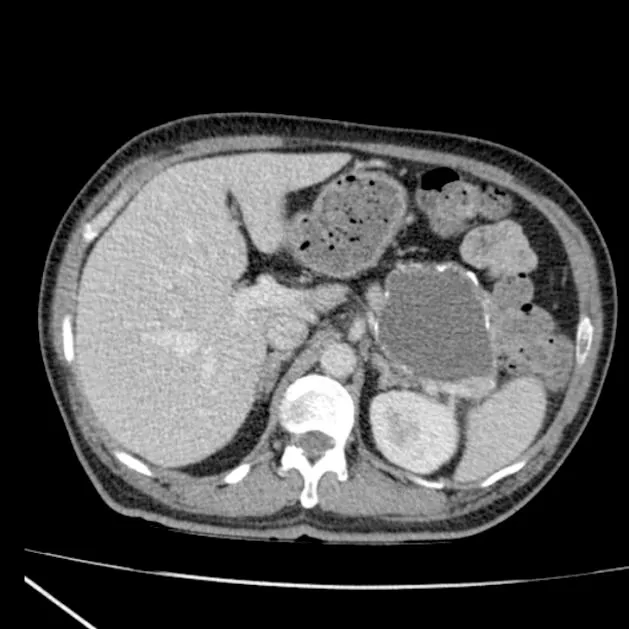

Gross: Multiloculated, microcystic ("honeycomb" or "spongy" pattern).

- Often has a central, stellate fibrous scar (may show calcification).